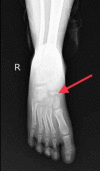

Kohler's disease is characterized by osteochondritis of the navicular bone due to various factors like the lack of blood supply and late ossification of the bone. In particular, it is a disease of the pediatric age group, which has male preponderance. It may present with bony pain unilaterally or, at times, be asymptomatic and diagnosed accidentally. Clinical presentation and radiological investigations are the mainstay of diagnosis. This self-limiting condition requires only symptomatic conservative management. A surgical approach is not yet indicated. One such case of bilateral Kohler's disease is presented in this report. Here, we discuss the disease's presentation, examination, treatment, and prognosis.